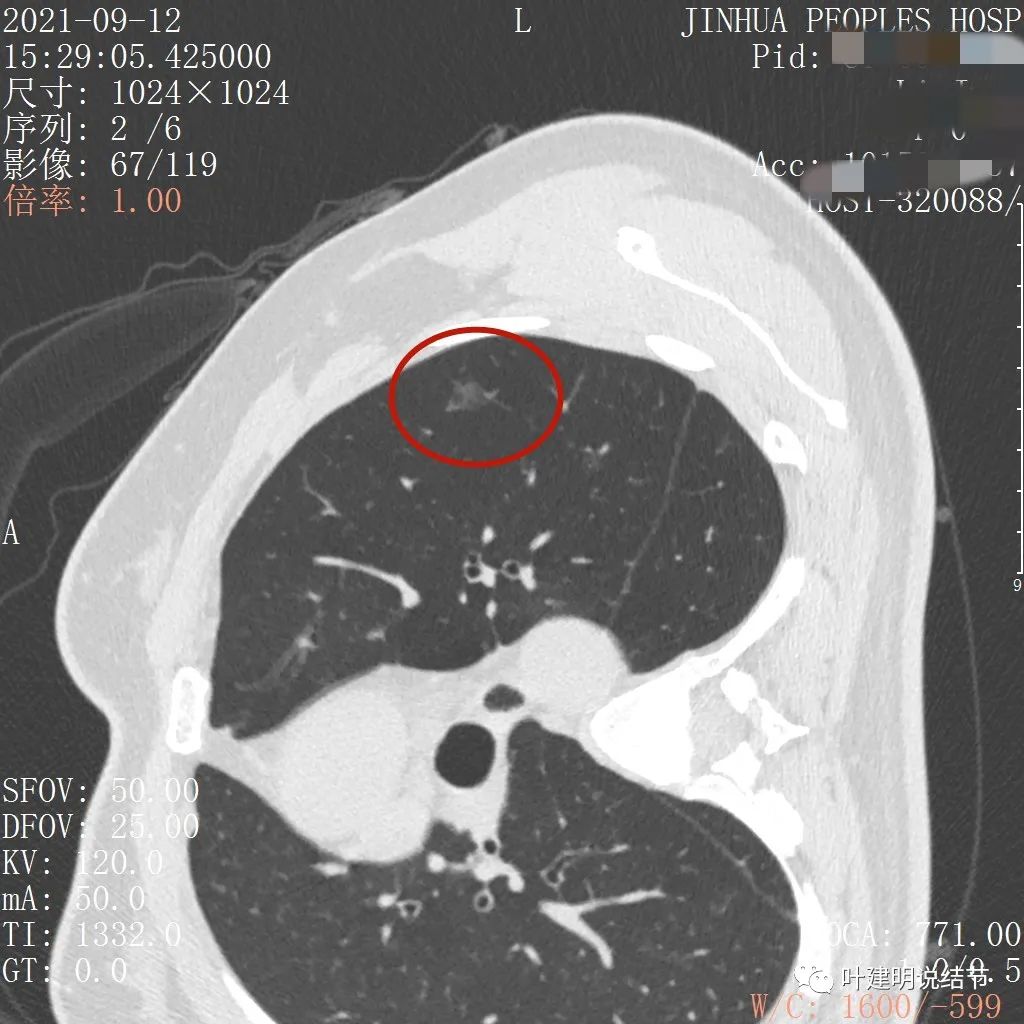

病灶整体密度较低,但轮廓较清,内部密度不大均匀,显得杂乱

不均质的偏低密度磨玻璃结节,轮廓清